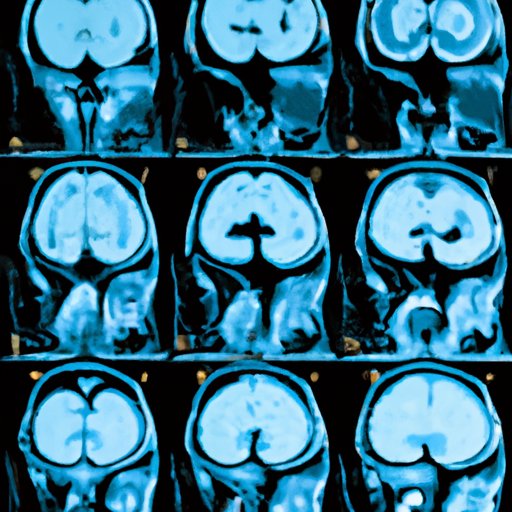

The Role of Imaging Tests in Identifying Brain Tumors

If going to the doctor is the next necessary step, your physician may suggest imaging tests. Different imaging tests are available for identifying brain tumors, such as MRI, CT scan, and PET. Understanding the differences between each test is critical to adequate diagnosis.

The tests primarily differ in terms of speed, efficiency, and level of detail in diagnosis. A CT scan is a quick and efficient way of identifying brain tumors, while an MRI provides more detailed information on the size and location of the tumor.

Your doctor will help you make the best decision concerning which test is suitable. When taking tests, the patient lies down on a table that slides into the imaging machine. The process typically takes between 30 minutes to an hour, after which patients can resume regular activities.